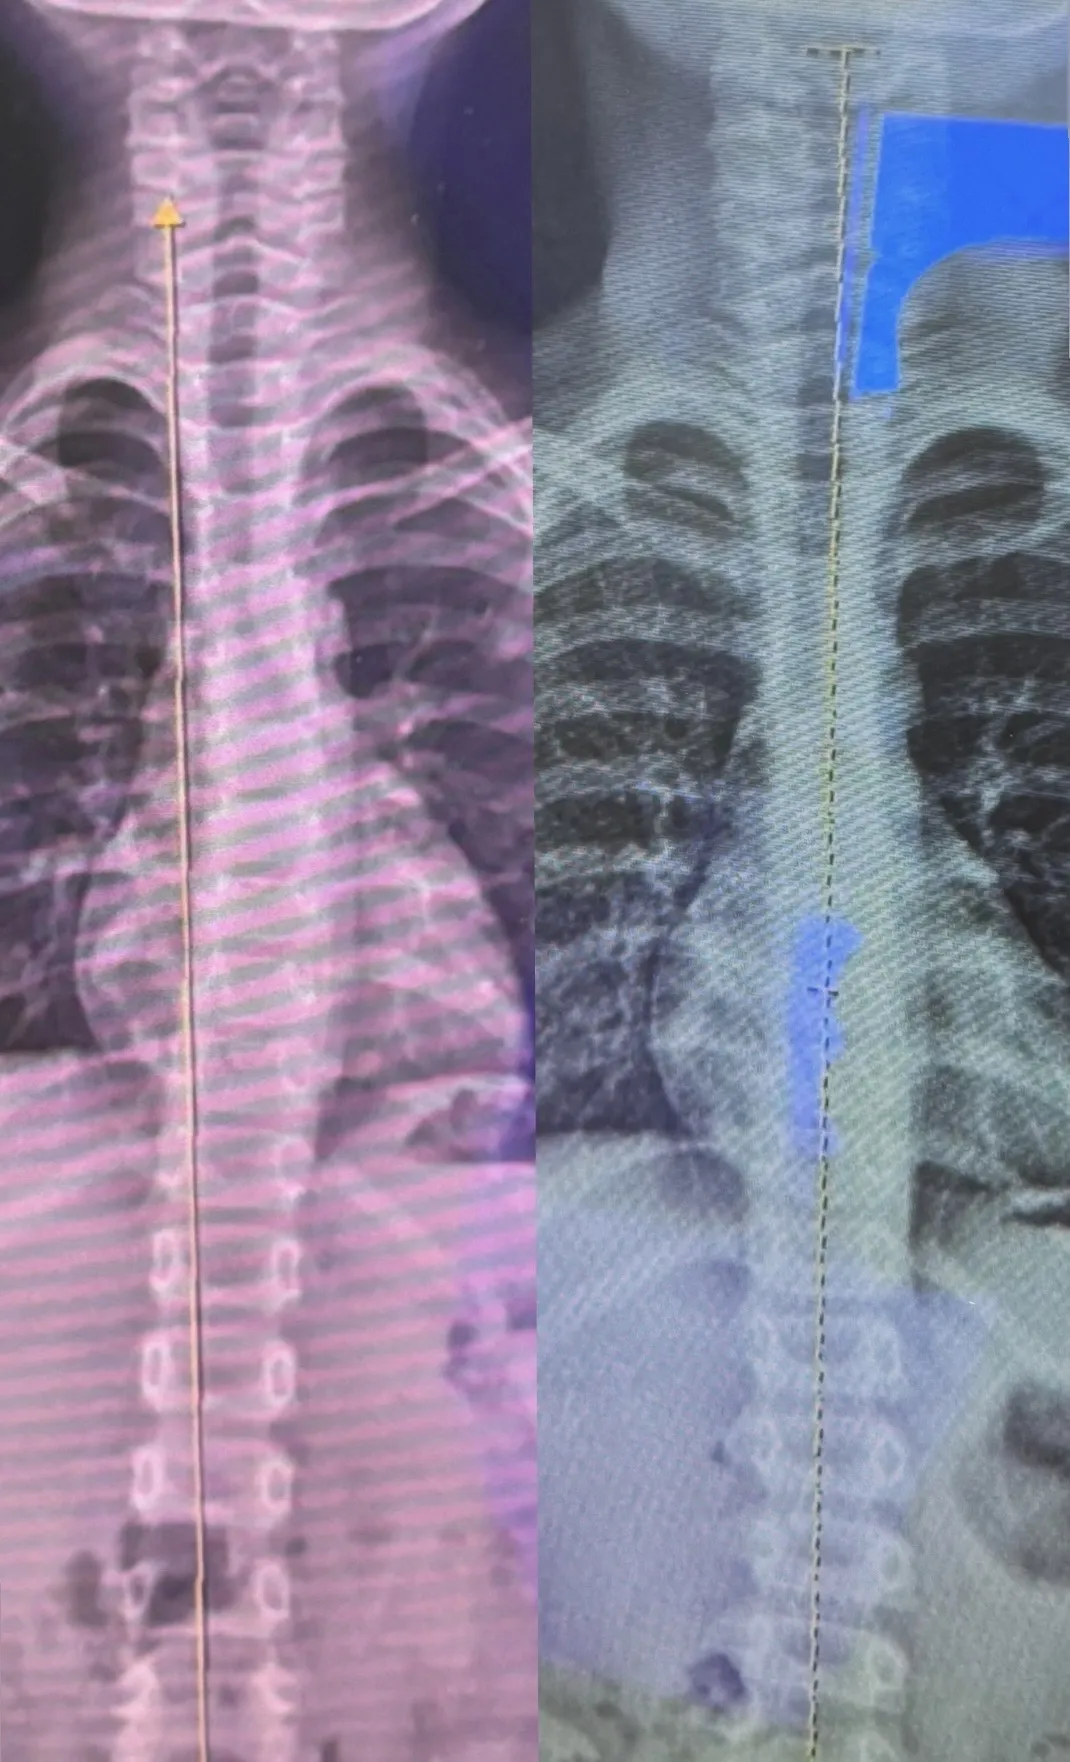

⒈影像學表現: 根據 12 月 X 光複檢,脊椎排列結構較前次有明顯改善。